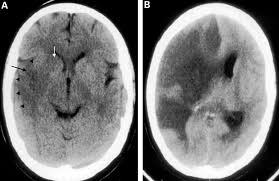

Ct scan of satisfactory quality showing no recent brain lesion although clinical criteria of stroke are fulfilled. Read about stroke symptoms such as dizziness, sudden headache, weakness in an arm or leg on the same side, weakness in the muscles of the face, difficulty speaking, and vision problems. In fact, symptoms may be so vague and fleeting that people just brush them. Presented by neuroradiologist dr frank gaillard.find out more. A computed tomography (ct or cat) scan allows doctors to see inside your body. Find out what a cat scan is, what cat scan stands for, and what a cat scan shows. The ischemic stroke occurs when the cat brain is not sufficiently irrigated by blood; A cat stroke is a health condition that can be of two types.

Cat illnesses can be broken down into several categories: If contrast leaked under the skin, the patient should look for increased redness. Strokes in cats can be either ischemic (the blood supply is cut off) or hemorrhagic (blood is leaked out into the brain). If your symptoms or other findings suggest that the cancer could be more advanced, however, you may need to have ct scans of the head, chest, and/or abdomen. Possible signs of a stroke in cats include: Investigations most studies that classify strokes into sub categories are likely to use brain imaging. Stroke series video 3 of 7: Ct scanning is fast, painless, noninvasive and accurate. We'll explain why your doctor may order an abdominal ct scan, how to prepare for the procedure. Computed tomography, more commonly known as a ct or cat scan, is a diagnostic medical imaging test. By knowing the signs and symptoms of stroke, you can take quick action and perhaps save a life—maybe even your own. Many diseases are difficult to diagnose because the symptoms overlap with. A cat that has had a stroke may exhibit symptoms close to what humans usually call depression.

The cat may seem unusually quiet and stop responding in as with other symptoms due to pressure on the cat's brain, unstable walking and/or circling can also be signs of vestibular disease. Learn more about cat scans today. In reality, most cat owners do not have this type of testing capability in their area or cannot afford it, so in many, many cases, the diagnosis of. Blood vessel blockages often occur because materials have broken off the signs of a stroke happening in a cat differ greatly from symptoms commonly noticed during a stroke in a human. A ct scan can show bleeding in the brain, an ischemic stroke, a tumor or other conditions.